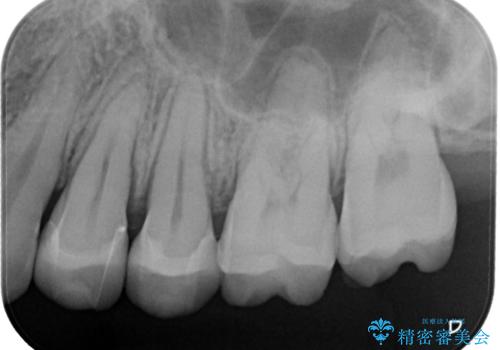

奥歯の着色が気になる セラミック治療

- 矯正終了後検査を行ったところ、以前詰めていたプラスチックの材料が着色し劣化していたこともあり、検査したところ虫歯になっていたところがあったため治療を進めることとなった。

劣化していたプラスチックをとって、虫歯をとり、形を作って、型取りをして、精度の高い詰め物(インレー)をしています。